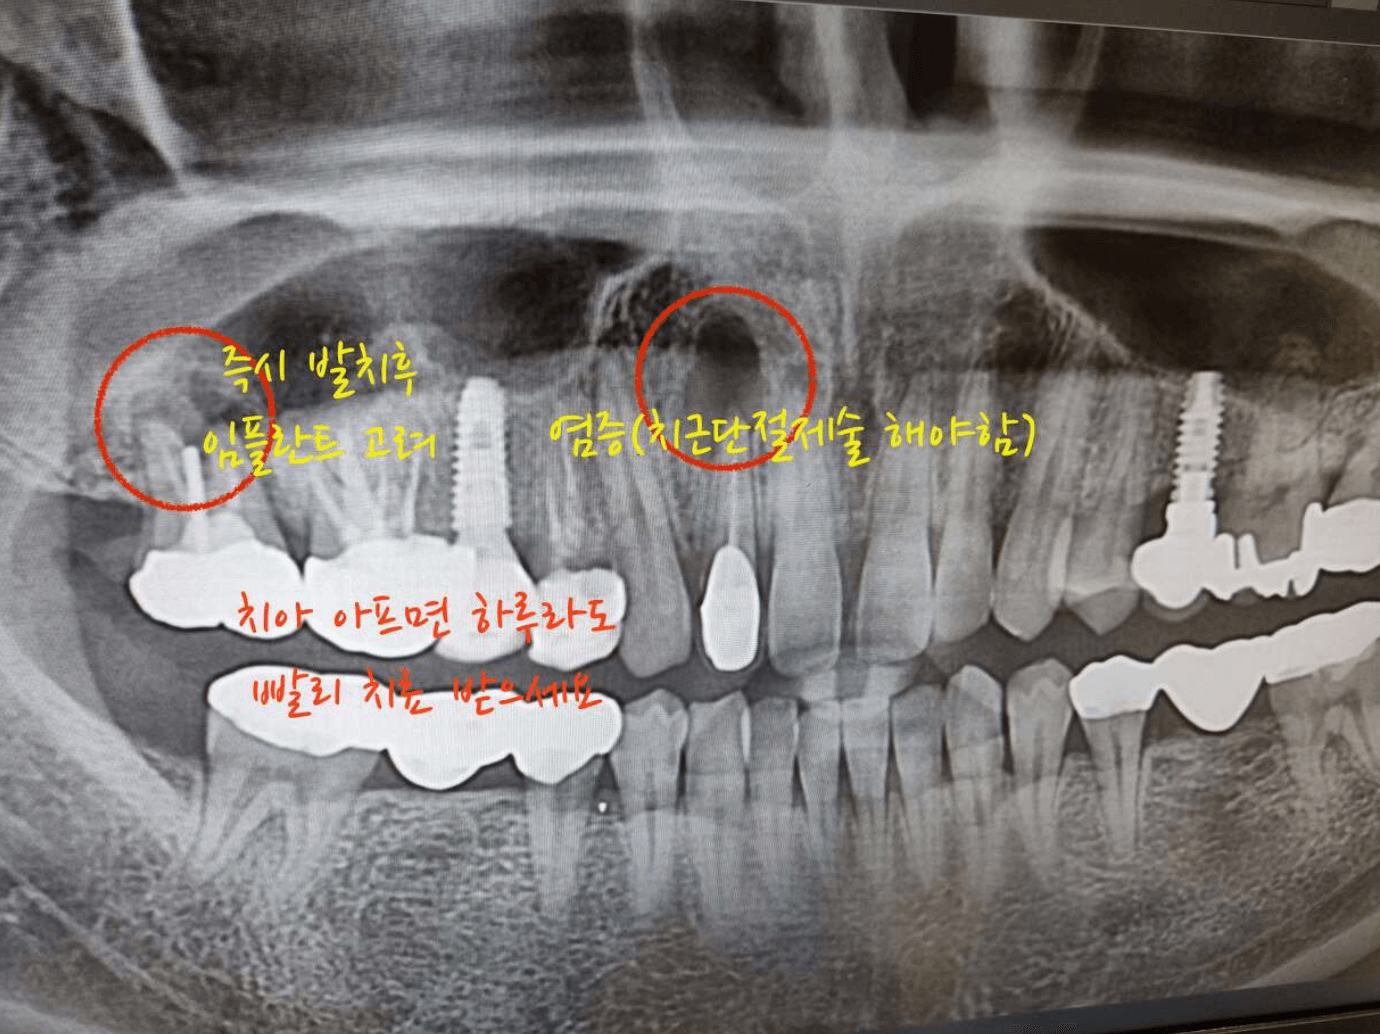

앞니쪽 크라운을 씌어놓은 치아가 염증이 생겨, 치아를 뽑지 않고 마지막 보류인 치근단절제술을 사용하여 치아뿌리를 잘라낸후 치아를 살리게 되었습니다. 이러한 치근단절제술 후기와 비용은 얼마나 들었고 보험적용 및 통증은 어느정도인지에 대한 경험자로써의 후기를 남겨 봅니다.

치근단절제술은 치아뿌리를 수술로 잘라내에 치아뿌리에 생긴 염증이나 낭종의 감염을 제거하여, 치아를 뽑지 않고 마지막 보류로 치아를 살리기 위한 수술입니다.

치근단절제술을 진행한 사람으로써, 생각보다 통증이 있으며, 수술후 글쓴이는 약간의 부작용이 생겨 아직도 잇몸이 치아사이로 끝까지 내려오지 않아 치아와 치아사이 잇몸이 비어있는 어색한 사항을 만들어 내고 있습니다.

개인적으로 이럴줄 알았으면, 차라리 그냥 임플란트를 하는것이 더 좋았지 않았나 합니다. 선택은 본인의 몫이고, 저처럼 치아는 살렸지만, 수술후 잇몸이 치아사이를 덮어주지 않아 치아가 벌어진것처럼 약간의 구멍이 났습니다. 아래 치근단절제술을 알아보면서 개인적 이야기도 더해 보겠습니다.

우려하던 일이 발생하게 되었습니다. 이전에 씌어놓은 앞니 크라운 치아 뿌리에서 큰염증이 발견되었고, 맨안쪽 크라운을 씌어놓은 어금니에도 염증이 생겨서 결국 어금니는 발치하고, 앞니 염